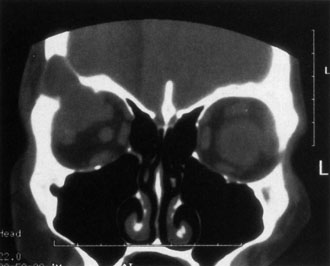

Contrast-enhanced CT of the orbits with direct and coronal cuts is the radiologic study of choice for these patients.45 A well-demarcated, encapsulated oval or rounded mass is revealed, which is typically intraconal in the lateral part of the middle third of the orbit (Fig. 5) but occasionally may extend to the extraconal space.42 Septa within the tumor may be apparent on high-resolution CT. The posterior pole of the globe frequently is indented by the rounded anterior margin of the tumor.42 The optic nerve typically is displaced rather than surrounded by the tumor. Subtle outward bowing of the lateral orbital wall or increase in orbital size may be present, consistent with a long-standing, slowly growing mass lesion.10,42 Enhancement with intravenous contrast occurs and may be homogeneous or inhomogeneous.10,45 Rarely, cavernous hemangiomas may occur as an intraosseous tumor within the orbital or facial bones.42,53–55 Although usually an isolated intraorbital lesion, multiple lesions in one orbit occurred in 8 of 164 (5%) patients of three combined large studies,10,42,45 and bilateral multiple cavernous hemangiomas also have been described.56 In contrast to patients with venous flow malformations in which phleboliths are common, phleboliths are rare in cavernous hemangiomas. Three large studies comprising 164 patients with cavernous hemangioma all reported that no calcification was detected within the tumor.10,42,45If the diagnosis is still unclear or if better definition of details and localization of the lesion is required, then MRI should be performed. Magnetic resonance imaging demonstrates nonspecific characteristics of a lesion isointense to muscle and gray matter on T1-weighted images and hyperintense on T2-weighted images (Fig. 6).57 The lesions show initial central patchy enhancement, which fills up homogeneously within 20 to 60 minutes.58 If ultrasonography is performed, B-scan ultrasonography shows a well-circumscribed mass with a sharply defined anterior acoustic border.23 A-scan ultrasonography shows high reflectivity of the echo signals resulting from the multiple blood-filled vascular channels, regular internal structure with a higher anterior and posterior spike marking the capsule, and moderate sound attenuation (angle of decrease of the echo spike within the lesion).24 Arteriography is not indicated.

Fig. 6. Cavernous hemangioma. Axial magnetic resonance imaging demonstrates a well-defined, homogeneous intraconal mass that is isointense to muscle and gray matter on T1-weighted image (A), and hyperintense on T2-weighted image (B). Note the displacement of the optic nerve and indented posterior globe.